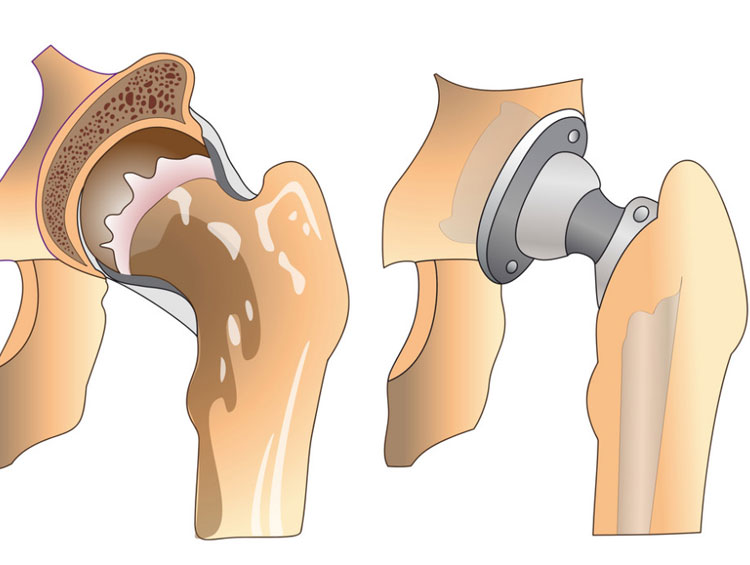

Ендопротезування кульшового суглоба

Первиннм класичним або малоінвазивним методом SuperPath або Bikini (розріз шкіри 8-10 см) у пацієнтів з артрозом, асептичний некроз головки стегнової кістки, переломами шийки стегна, дисплазією і т.д.

Середній термін перебування пацієнта в клініці 3-4 дня.

Ціна операції в клініці з протезом від 85 тис гривень

Заміна компонентів зруйнованого протезу, перипротезні переломи

Ревізійне ендопротезування на відміну від первинної операції - більш складна і більш тривала процедура. Термін перебування в клініці визначається індивідуально.